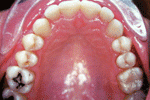

มาถึง การจัดฟันด้านใน

การจัดฟันแบบใสและขั้นตอนการจัดฟันมีรูปคนน่ารักจัดฟันด้วย    การจัดฟันแบบใสและขั้นตอนการจัดฟันมีรูปคนน่ารักจัดฟันด้วย       การจัดฟันแบบใสและขั้นตอนการจัดฟันมีรูปคนน่ารักจัดฟันด้วย

การจัดฟันแบบใสและขั้นตอนการจัดฟันมีรูปคนน่ารักจัดฟันด้วย   >>  การจัดฟันแบบใสและขั้นตอนการจัดฟันมีรูปคนน่ารักจัดฟันด้วย  >> การจัดฟันแบบใสและขั้นตอนการจัดฟันมีรูปคนน่ารักจัดฟันด้วย

>>   การจัดฟันแบบใสและขั้นตอนการจัดฟันมีรูปคนน่ารักจัดฟันด้วย     >>>>>>>  การจัดฟันแบบใสและขั้นตอนการจัดฟันมีรูปคนน่ารักจัดฟันด้วย